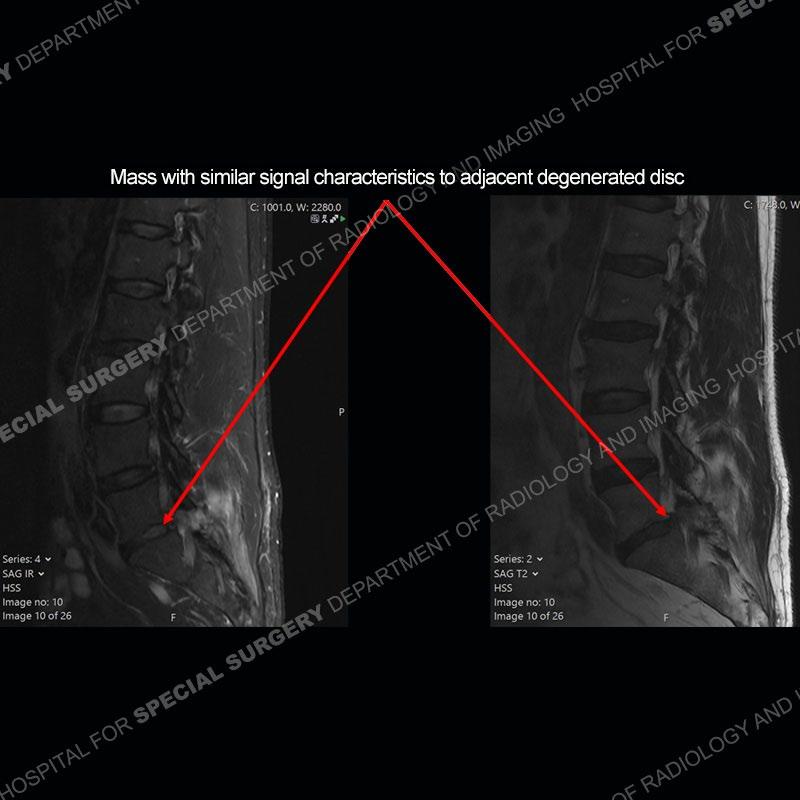

Post operative changes are seen on the left side at L5-S1 where there is near complete removal of the left sided L5 lamina, partial resection of the left L5-S1 facet joint, and resection of the left sided ligamentum flavum. In the anterolateral epidural space about the subarticular recess is a mass that demonstrates similar T1 and T2 signal characteristics to the adjacent degenerated disc. There is enhancement about the periphery of the mass, but the majority of this somewhat geographic or polyploid mass demonstrates no enhancement. The mass exerts prominent mass effect on the left S1 axillary sleeve/proximal nerve root. The left S1 nerve root shows enlargement and increased enhancement as compared to the contralateral right side.

Not as much of a diagnostic dilemma as some other cases but more so just a very nice example of what can be a difficult assessment at times. The evaluation of granulation tissue/scar/epidural fibrosis vs. disc herniation particularly in the earlier post operative period can be very difficult. Clues that can assist in identifying a disc herniation are a more geographic or polypoid nature to the mass, signal characteristics similar to the adjacent degenerated disc, mass effect upon the thecal sac/adjacent neural structures, and a typical enhancement pattern. As the disc material is avascular, as long as imaging is performed in a relatively rapid fashion after contrast administration (within 20-30 minutes), the granulation tissue around the disc will enhance but the disc material itself will not. If there is a marked delay between contrast administration and imaging, there may be diffusion of contrast into the disc making the assessment very difficult. The marked utility of contrast to help delineate disc vs. scar has led to our institution employing contrast fairly uniformly within the first two years following surgery.